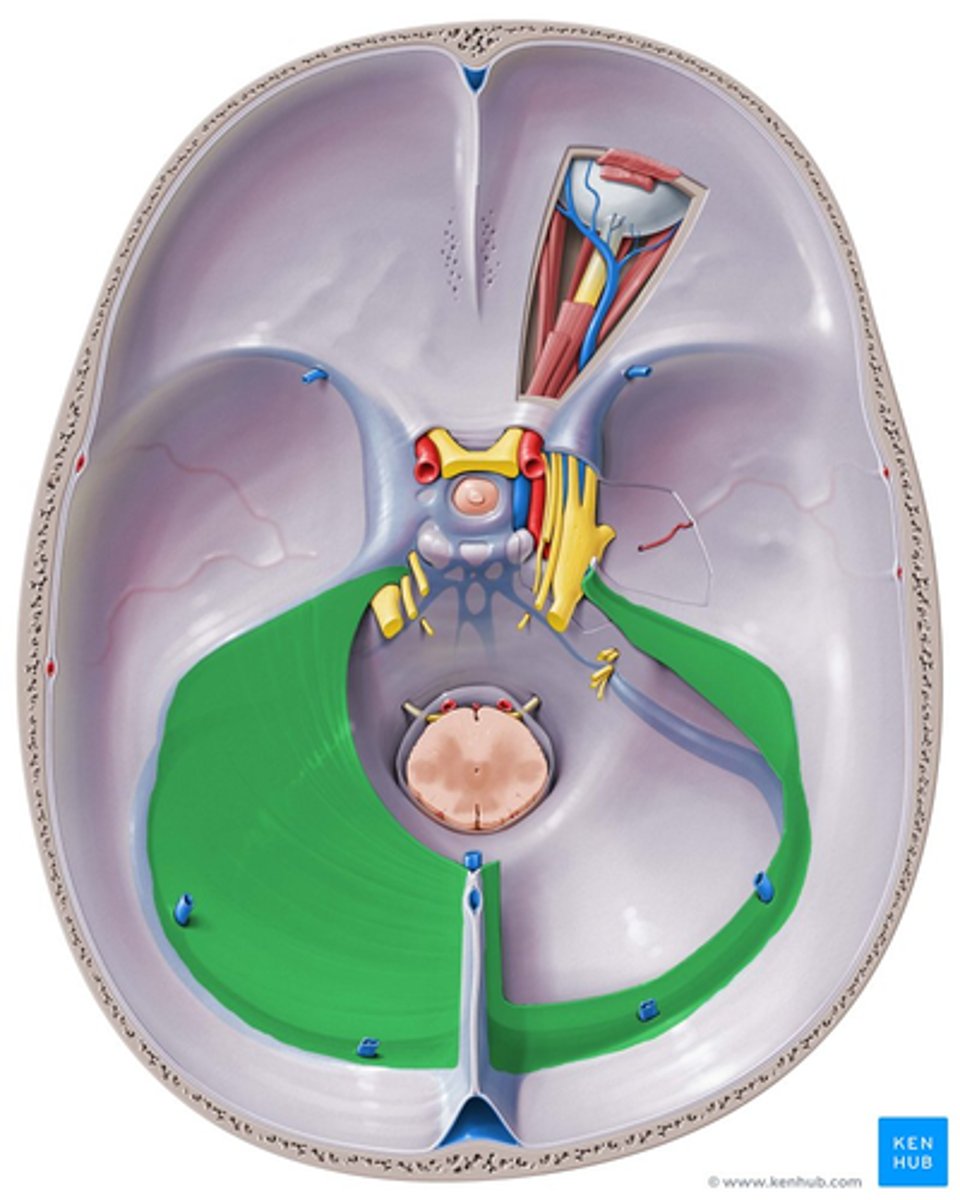

falx cerebri

sickle shaped, separates two hemispheres

tentorium cerebelli

shelf-like, separates cerebellum from cerebrum

tentorium cerebelli

falx cerebri